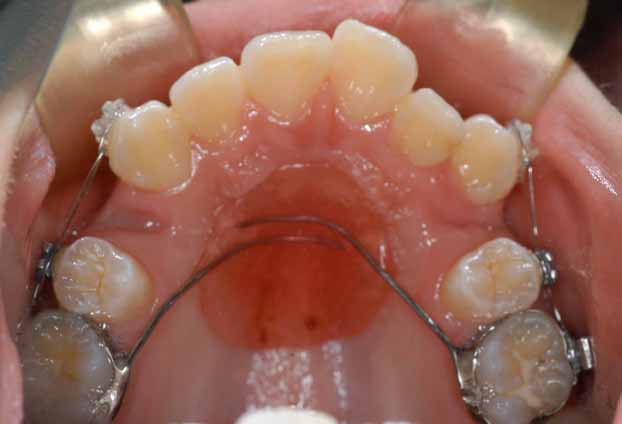

3.下顎前突(受け口) 下の歯が上の歯より出ています

治療前

上の八重歯が並んだ状態です